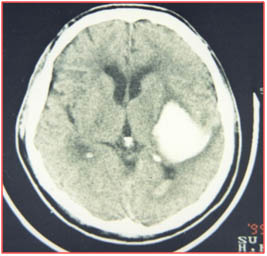

腦出血微創(chuàng)置管術,通過術前、術中精確定位,能夠很好地確定血腫部位,并避開重要腦組織功能區(qū)及重要血管,對周圍腦組織幾乎沒有影響,把手術創(chuàng)傷降到了最低。手術優(yōu)點是能夠有效的清除血腫,最大限度的減少周圍組織的損傷,及時解除了腦出血占位,降低了顱內壓,阻斷了腦出血后一系列繼發(fā)性病理生理改變所導致的惡性循環(huán)。對減輕腦水腫、防止再次出血,防治肺部感染、上消化道出血等并發(fā)癥的發(fā)生有顯著作用。由于手術創(chuàng)傷小、手術時間短、血腫引流確切,患者恢復快、住院時間短、花費少。改變了以往傳統(tǒng)開顱手術風險高,手術時間長,患者創(chuàng)傷大,并發(fā)癥多,恢復慢的問題。

術后第10天